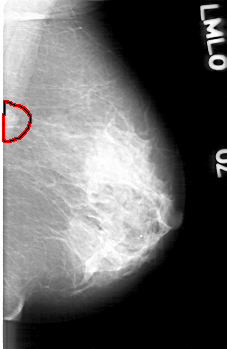

D_4088_1.LEFT_MLO

LEFT_MLO LINES 5221 PIXELS_PER_LINE 3391 BITS_PER_PIXEL 12 RESOLUTION 43.5 OVERLAY

FILE: D_4088_1.LEFT_MLO.OVERLAY

TOTAL_ABNORMALITIES 1

ABNORMALITY 1

LESION_TYPE MASS SHAPE IRREGULAR MARGINS ILL_DEFINED

ASSESSMENT 0

SUBTLETY 4

PATHOLOGY BENIGN

TOTAL_OUTLINES 1

BOUNDARY